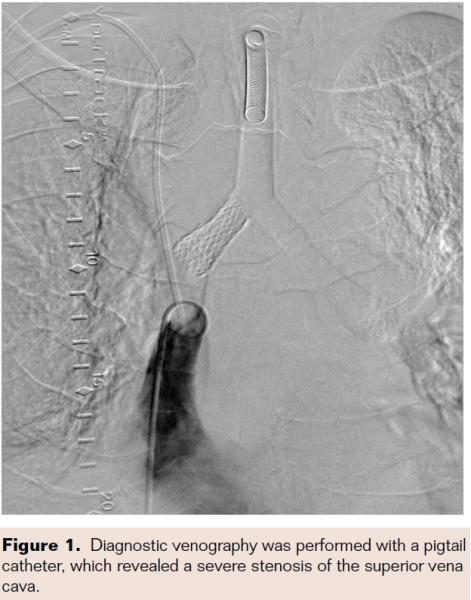

The right femoral vein was punctured and a 7 Fr introducer sheath was placed. Diagnostic venography was performed with a pigtail catheter, which revealed a severe stenosis of the SVC (Figure 1). Subsequently, a 6 Fr sheath was inserted in the right jugular vein using ultrasound guidance. The area of stenosis was crossed with a 0.014˝ Asahi Prowater wire (Abbott Vascular) via the right jugular vein. The patient was heparinized for an activated clotting time >250 sec. Intravascular ultrasound (Volcano, Eagle Eye platinum 3.5 x 150) was performed and demonstrated severe stenosis with reference vessel diameter of 8.0 mm (Figures 2A and 2B). The port-a-cath was located in the area of potential stenting. We used a 4-8 mm EnSnare (Merit Medical, Inc) from the right internal jugular vein to snare and then retract the tip of the port-a-cath cephalad. While the catheter was retracted, an 8 x 38 mm balloon-expandable iCAST covered stent (Atrium) was deployed at the site of stenosis through a right femoral vein access sheath (Figure 3). This stent was postdilated with a 10 x 40 mm Mustang balloon (Boston Scientific). Finally, the snared port-a-cath was repositioned within the lumen of the iCast stent in the SVC. Excellent angiographic results were obtained with no residual stenosis. There were no complications. The symptoms markedly improved within 24 hours and he was discharged on anticoagulation therapy. The patient died 3 months following the procedure.